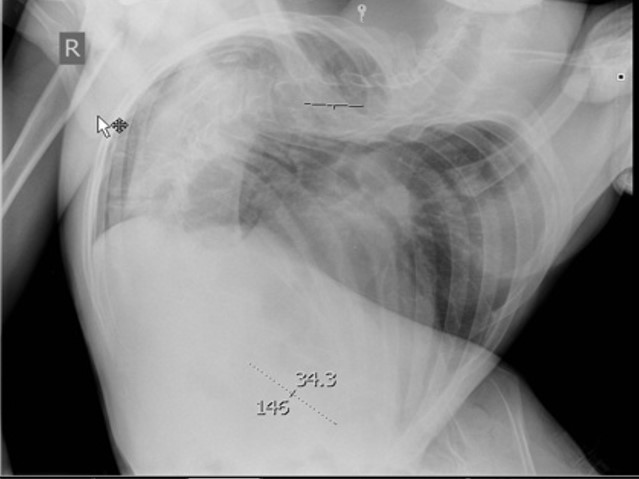

Особенности ведения периоперационного периода пациентов с декомпенсированным сколиозом глазами врача анестезиолога.

Физическое состояние пациента